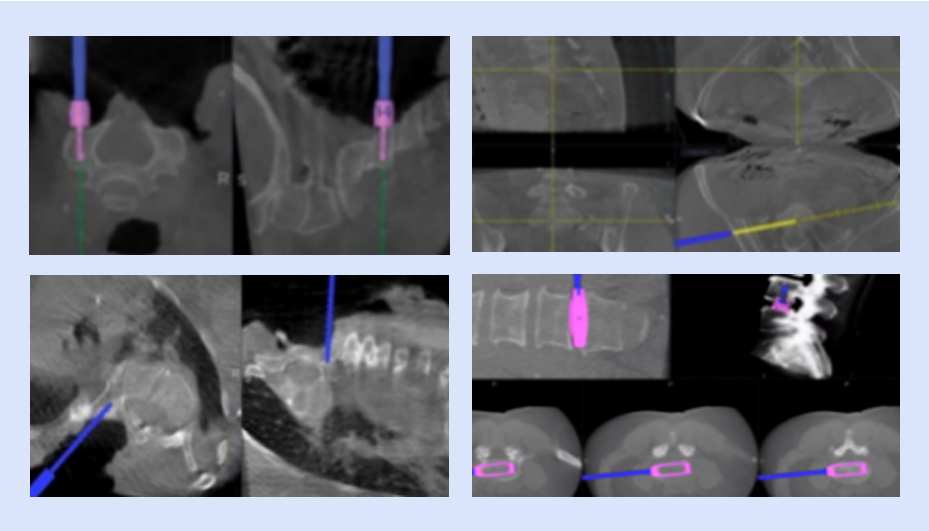

可视化置钉

确保导航设备正常运行,检查定位系统、手术器械、置钉系统等是否完好,以及设备是否处于最佳工作状态